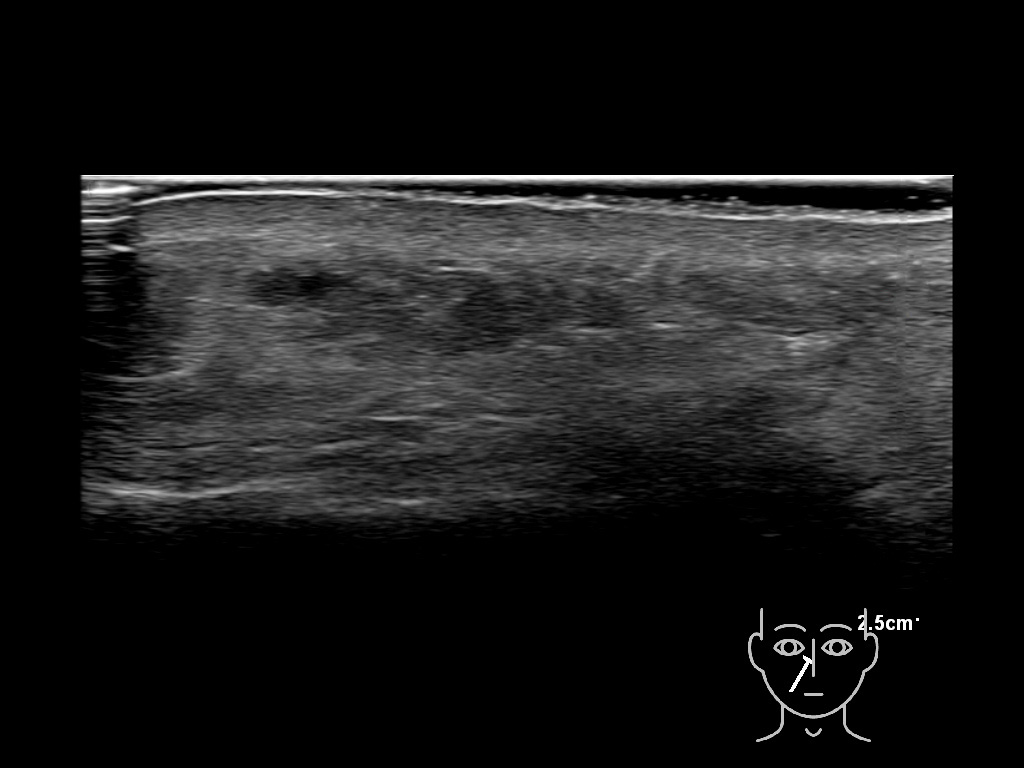

With ultrasound signs of inflammation can be visualized. Edema can be seen as a hyperechoic appearance of the subcutaneous fat, sometimes separated by hypoechoic fluid filled area’s, known as cobblestone appearance. Increased vascularization (hypervascularity) can be seen on colour Doppler. An abscess will appear as a fluid collection appearing as an irregular hypoechoic area with heterogeneous internal echoes and a thickened wall. Posterior acoustic enhancement can be present, and there is vascularity around but not within the mass. Under ultrasound guidance, abscesses can be managed by needle aspirations (18G) under antibiotic cover.

Study the first image to recognize the different layers. If you are sure about the layers, swipe to the second image to view the answer (if applicable).